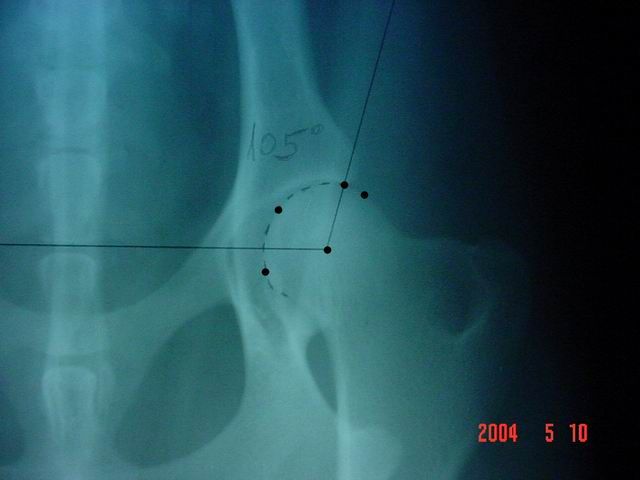

Kattintás=nagyításNormál az az ízület, amelynél a vápa félkör alakú, a combcsontfejet nagyobbrészt magában foglalja, az ízületi rés keskeny, egyenletes tágasságú, a Norberg-féle mérés szerinti szög 105° vagy annál nagyobb. Az ízületben, illetve környékén semmiféle gyulladásra utaló tünet nincs.